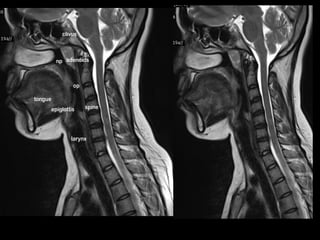

Case 5

• Left vocal cord palsy.

Thickening of aryepiglottic fold on left side.

Assymetric vocal cords

So , is there a mass in larynx..?

• Direct laryngoscopy – no mass.

• Remember that chages seen in MRI are

secondary to recurrent laryngeal palsy.

• They do not represent tumor.

• Larynx imaging findings should always be

correlated with laryngoscopy findings